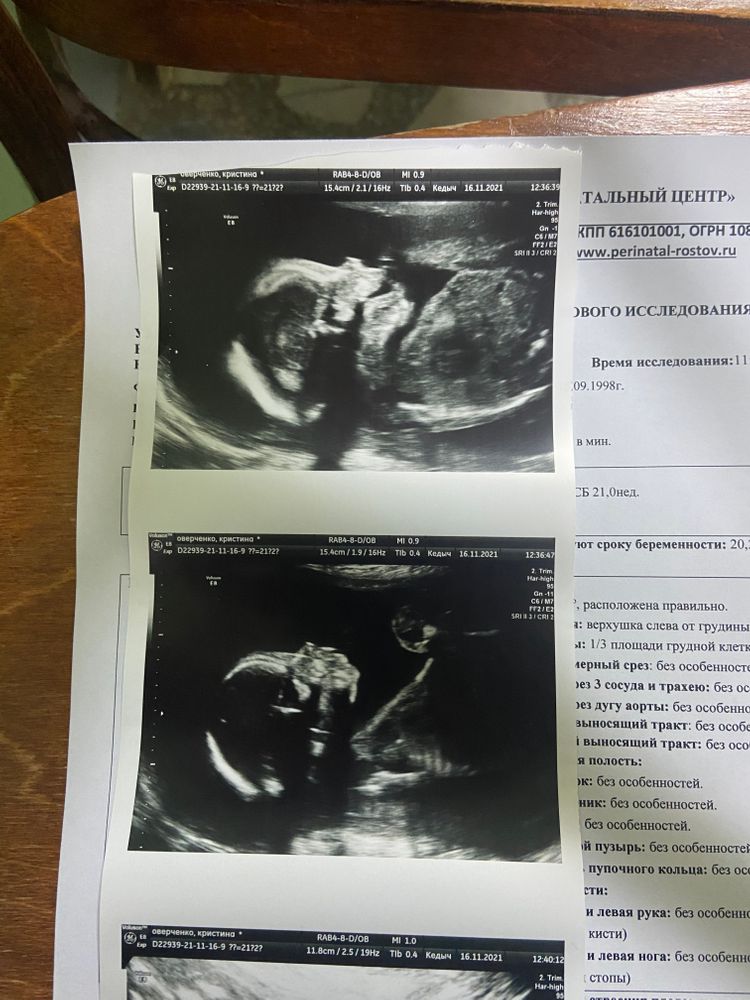

И так, второй скрининг пройден..что же происходило до него? в 12 недель предположили девочку, в 21 неделю подтвердили, заболела ковидом на 17 неделе, состояние было ужасное, сейчас более менее восстанавливаюсь, на 19 недели начала ощущать первые шевеления, начал резко расти живот, побаливать поясница, а так же я поняла что такое тонус. Далее перейдем ко второму скринингу, ох и намучалась я сегодня у кабинета узи. Первый раз зашла сказали лежит неудачно и нужно идти кушать сладкое (пошла съела мафин шоколадный с чаем), второй раз пошла все померили кроме носа, так как не поворачивалась малышка, сказали постоять (простите раком), но и это не помогло, отправили пить ношпу и ходить, на третий раз о чудо все замерили и все хорошо. На второй скрининг мужа не пустили, скорее всего из за ковида, а я его вызволила с работы, конечно хотела чтобы и он посмотрел. Кстати на 6-7 недели выкладывала пост с узи и спрашивала девчонок о методе Рамзи по определению пола и все как один говорили что будет мальчик, только 1-2 человека сказали что девочка и они оказались правы) Прикрепляю фото на память 🥰